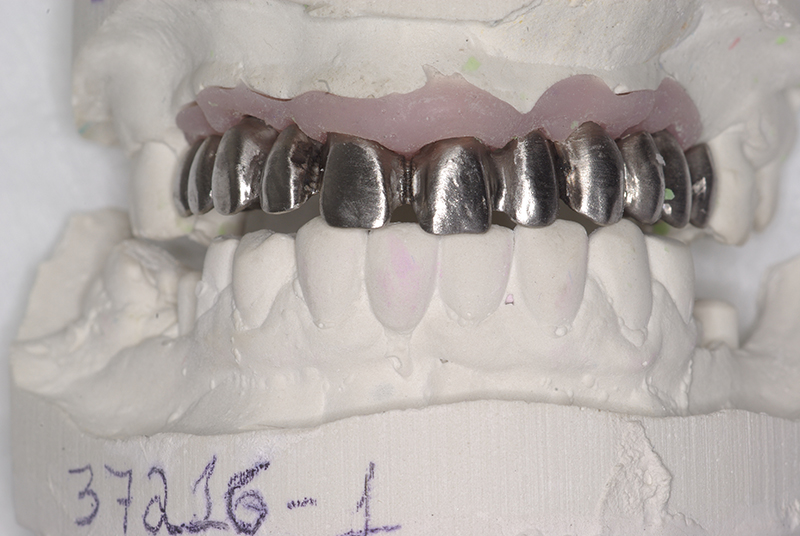

Tecnologia CAD CAM para Maior Precisão e Conforto

Utilizamos a tecnologia CAD CAM, um sistema avançado que possibilita a confecção precisa das próteses dentárias diretamente sobre os implantes. Esse método inovador garante um ajuste perfeito, um resultado estético superior e proporciona muito mais conforto e durabilidade. Com o CAD CAM, nossos pacientes contam com um processo mais rápido e previsível para alcançar o sorriso desejado.